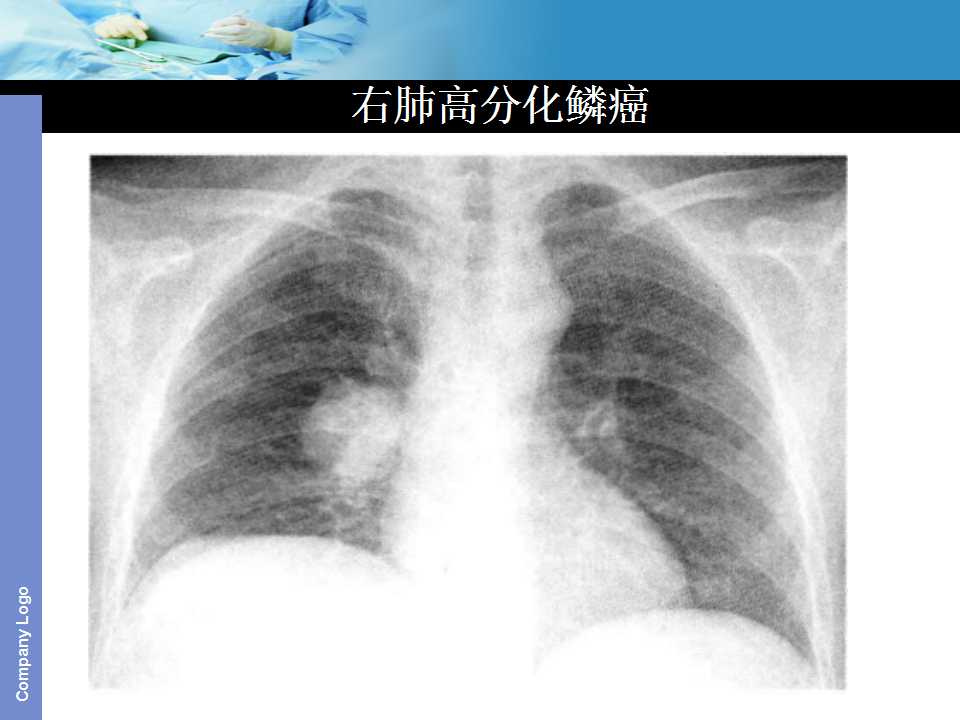

肺癌影像诊断